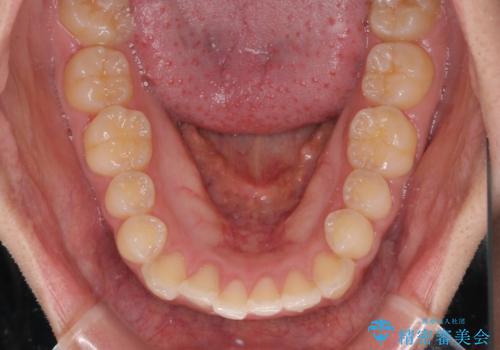

- 口が閉じにくさを気にして来院された患者様です。

上下の前歯が前方に突出していたため、上下左右の第一小臼歯4本を抜歯し、ワイヤー装置にて抜歯矯正を行うこととしました。

上下前歯部の被蓋関係を改善するの時間がかかり、3年間を要することとなりましたが、スッキリとした口元に仕上がりました。